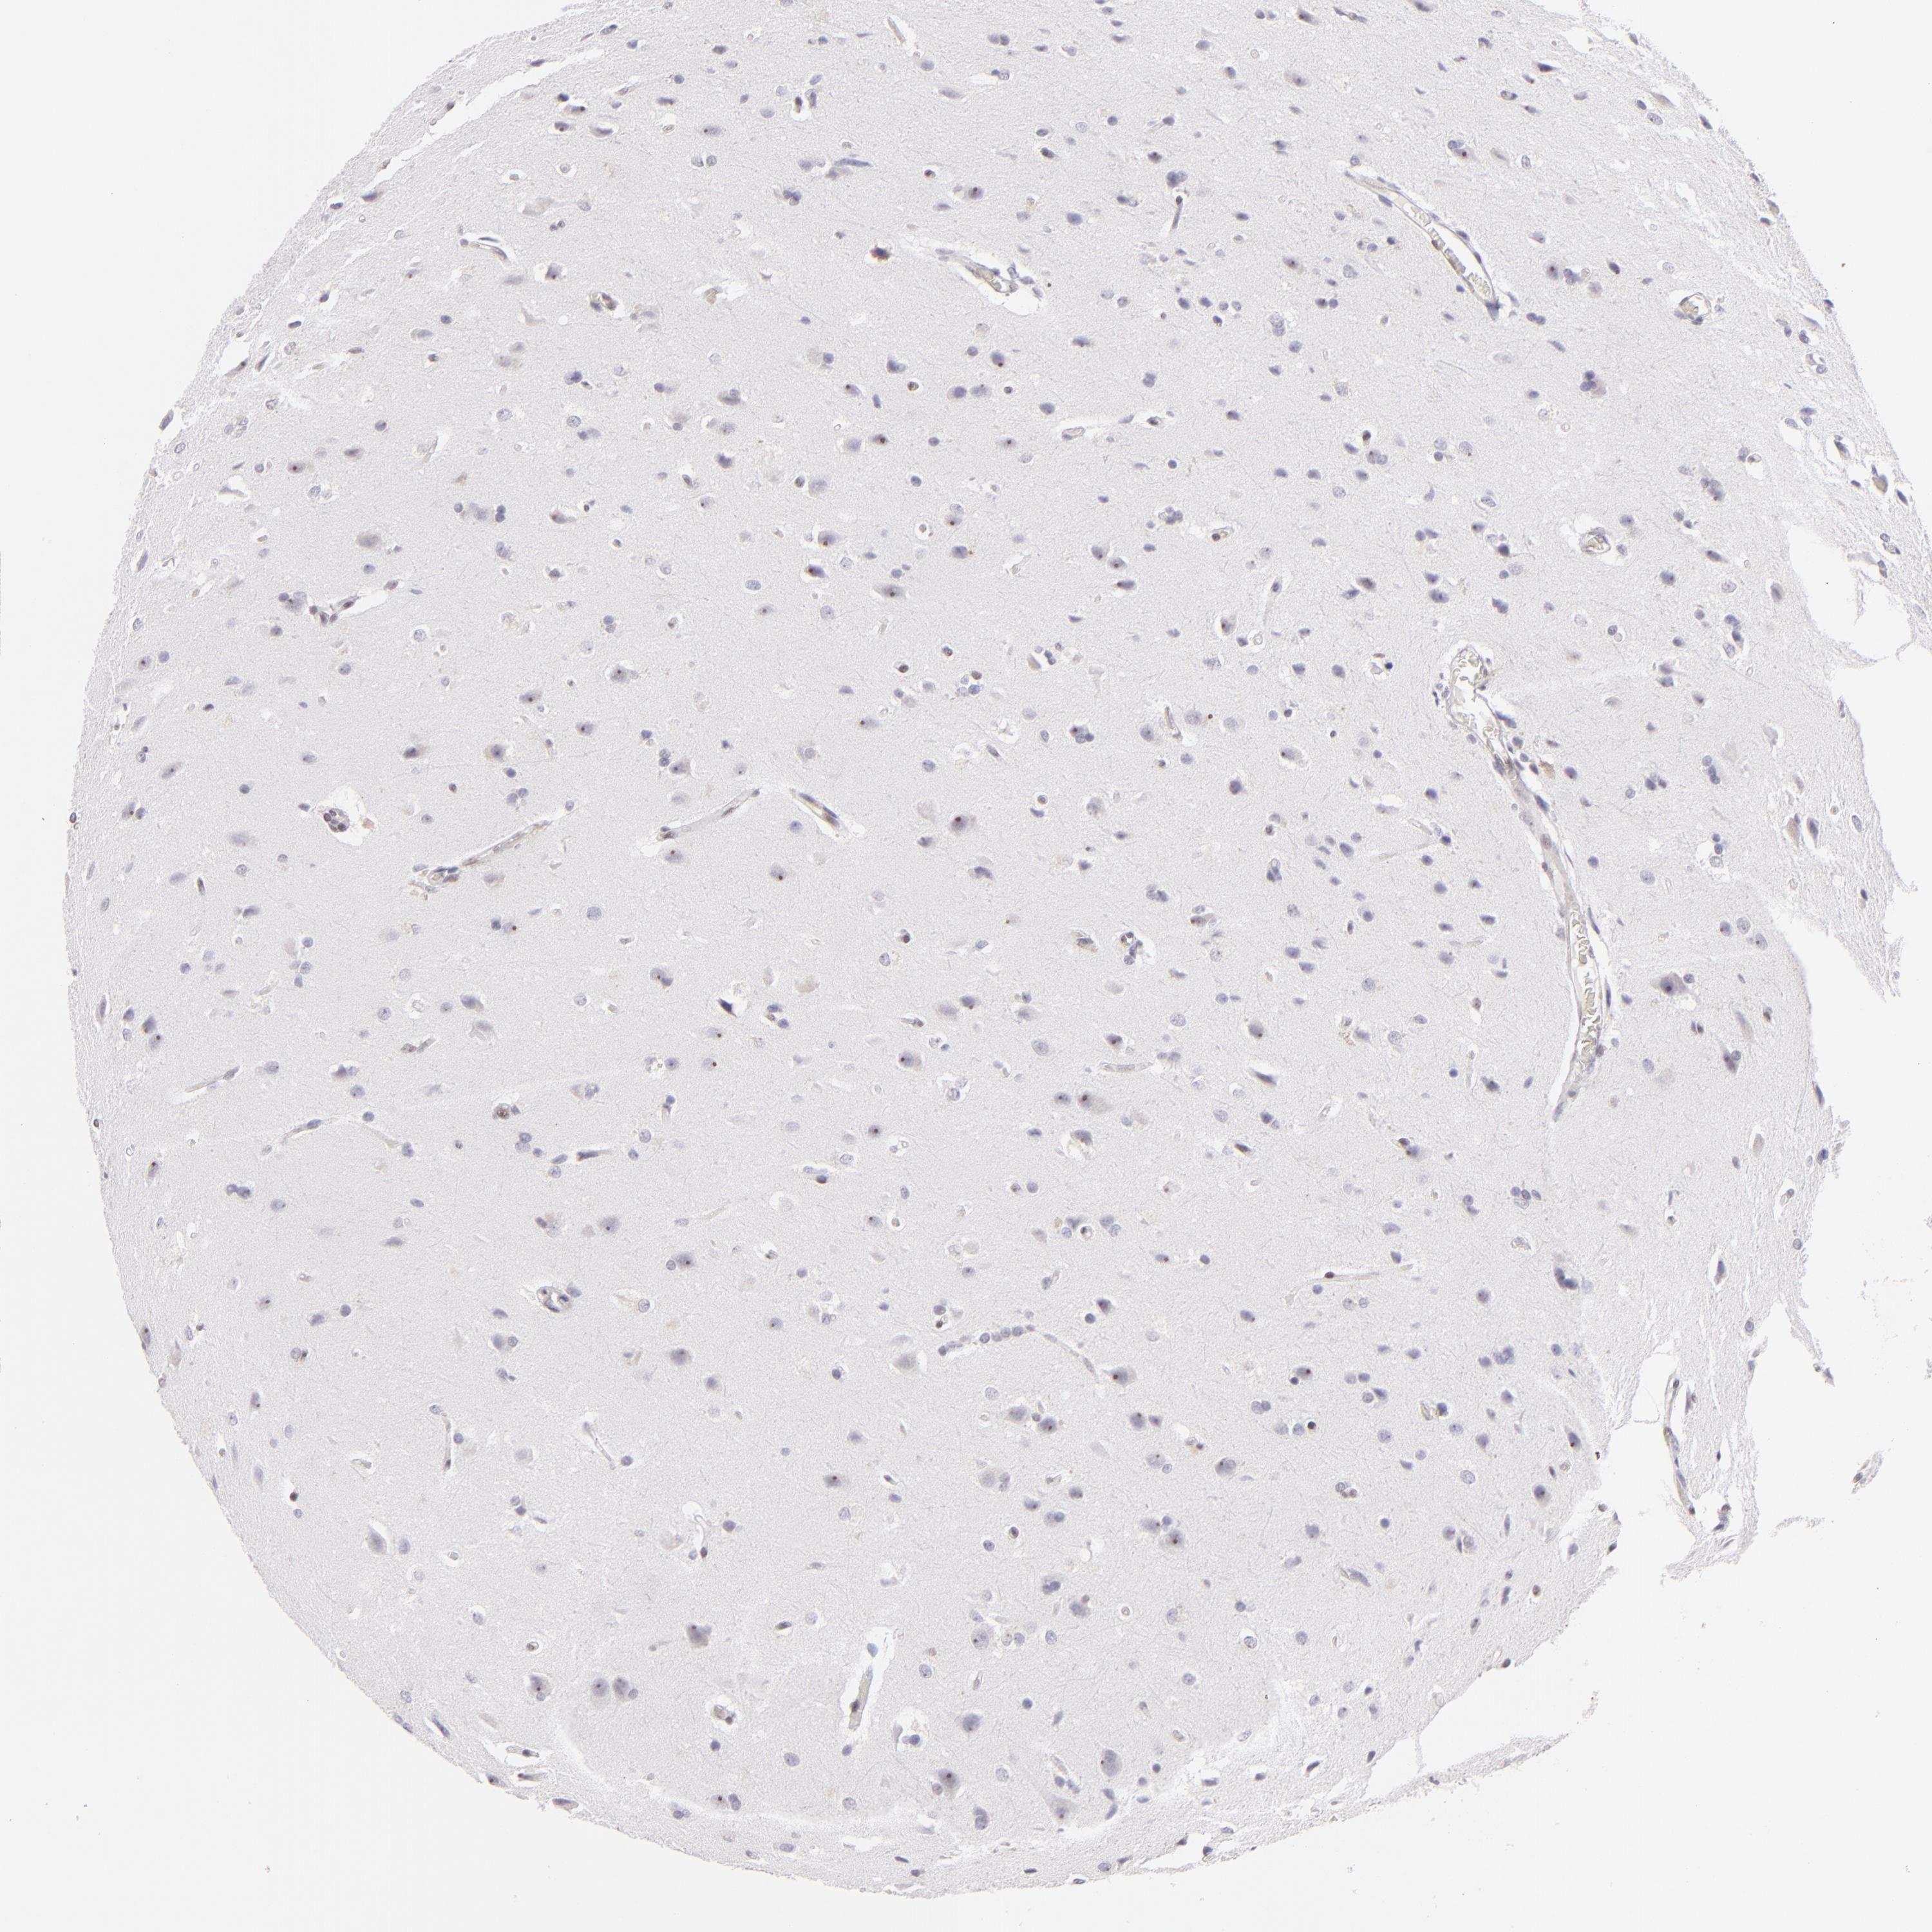

GLIOMA - Protein expressioni

A mouse-over function shows sample information and annotation data. Click on an image to view it in a full screen mode. Samples can be filtered based on level of antibody staining by selecting one or several of the following categories: high, medium, low and not detected. The assay and annotation is described here.

Note that samples used for immunohistochemistry by the Human Protein Atlas do not correspond to samples in the TCGA dataset.

Antibody stainingi

Antibody staining in the annotated cell types in the current human tissue is reported as not detected, low, medium, or high, based on conventional immunohistochemistry profiling in selected tissues. This score is based on the combination of the staining intensity and fraction of stained cells.

Each image is clickable and will lead to virtual microscopy that enables deeper exploration of all samples and also displays staining intensity scores, fraction scores and subcellular localization as well as patient and tissue information for each sample.

Antibody HPA064323

Antibody CAB002608

Staining

High

Medium

Low

Not detected

Intensity

Strong

Moderate

Weak

Negative

Quantity

>75%

75%-25%

<25%

None

Location

Nuclear

Cytoplasmic/membranous

Cytoplasmic/membranous,nuclear

Glioma, malignant, Low grade

Glioma, malignant, High grade